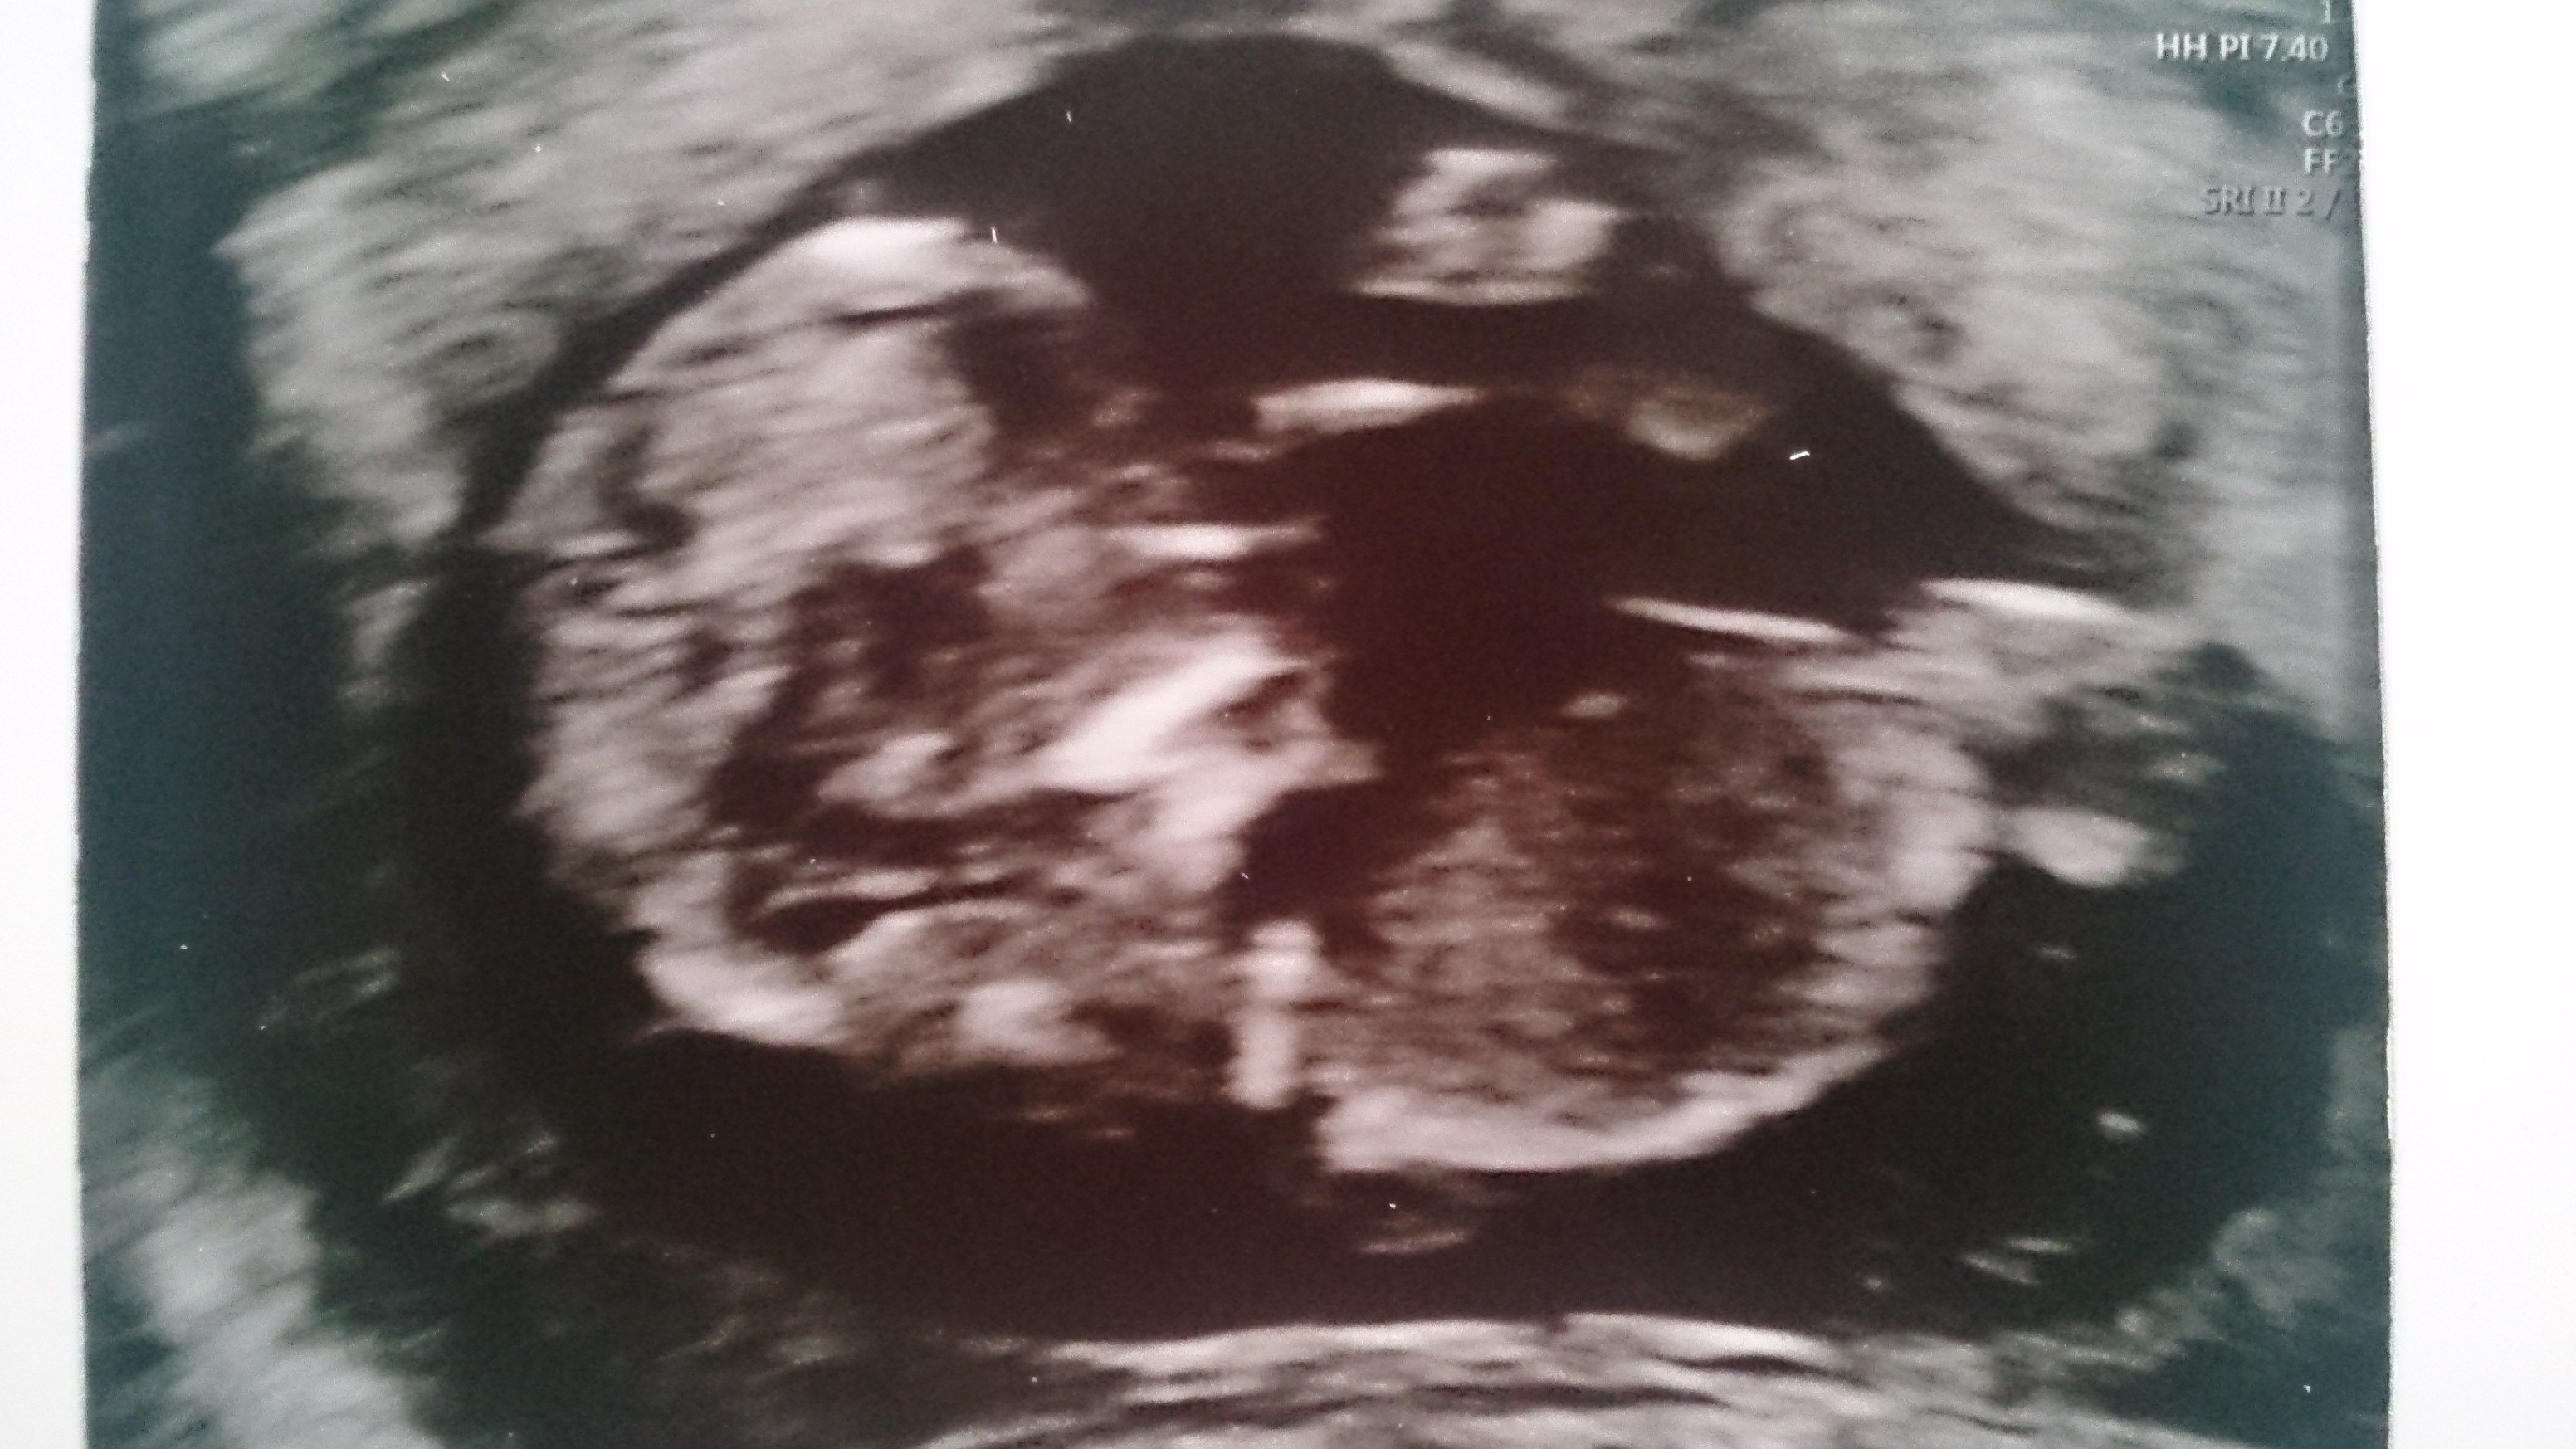

Nasze 5.26cm szczęścia :)

Miałam dziś prenatalne wszystko w porządku NT 0.13 z usg wychodzi 11+6.

Idąc dziś na wizytę nie spodziewałam się tego ze poznamy płeć:)

Na usg tak wszystko było ładnie widać że ja nie znając się bym też tak powiedziała jak lekarz, zobaczymy czy na dalszych wizytach będzie się potwierdzać :) ( chociaż tam gdzieś z tyłu głowy mam myśl że może to za wcześnie jeszcze, w pierwszej ciąży poznaliśmy płeć dopiero w 20tyg )

Nasze drugie maleństwo to chłopiec :) [emoji64][emoji173]